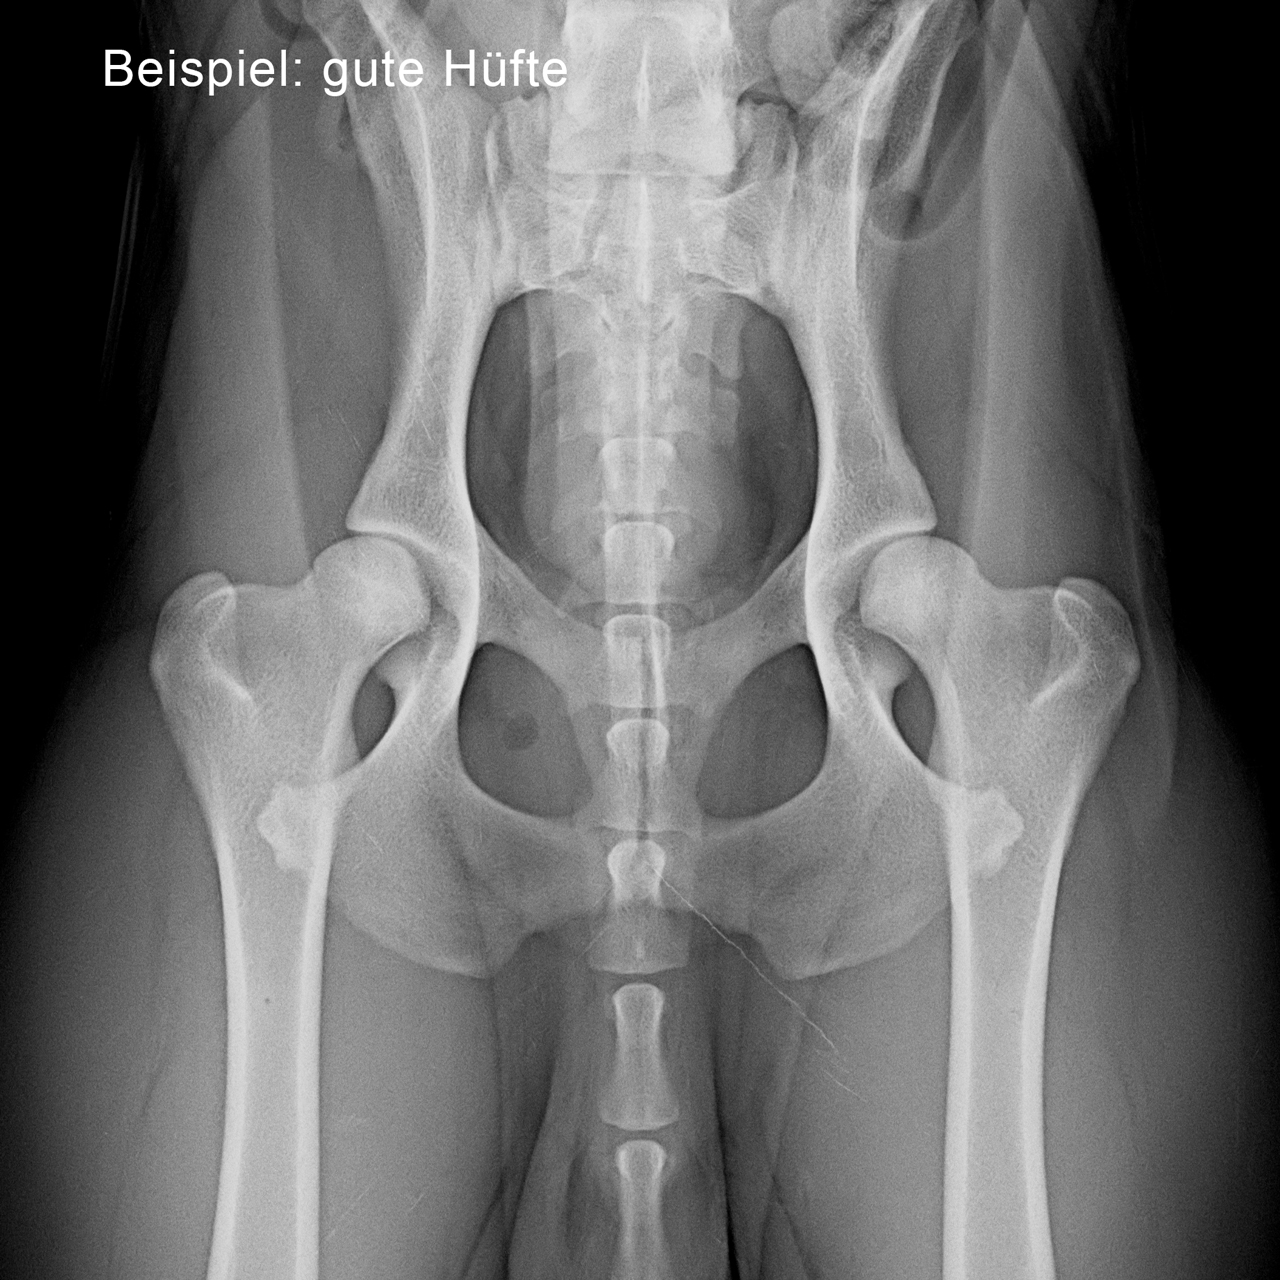

Graf Barf: Viele Züchter möchten für ihre Zuchtstatistik Röntgenaufnahmen des Welpen von Hüfte und Ellenbogen. Macht es generell Sinn, Junghunde röntgen zu lassen, um zu überprüfen, ob alles in Ordnung ist?

Dr. Susanne Wisniewski: Das stimmt, für die Ahnenstatistik und das Zuchtbuch der Züchter sollen alle Nachkommen überprüft werden, ob insbesondere Hüfte und Ellenbogen eine genetisch gesunde Disposition haben. Das ist gleichzeitig für die zukünftigen Welpenkäufer wieder ein sehr wichtiger Indikator. Dies geschieht dann, wenn der Hund ca. ein Jahr alt und ausgewachsen ist.

Hundebesitzern, die bereits schlechte Erfahrungen, z.B. mit schlechten Hüften oder Ellenbogen, gemacht haben – insbesondere bei großen Rassen mit Rassedispositionen –, kann man durchaus raten, ihren Welpen mit 5½ bis 6 Monaten einem orthopädisch geschulten Tierarzt vorzustellen. Der Tierarzt prüft das Gangbild und die Gebissstellung des Hundes und kann evtl. eine Röntgenaufnahme machen. Denn die Qualität der Hüfte kann jetzt bereits sehr gut beurteilt werden, und man kann unter Umständen im Ernstfall schon gezielt reagieren und helfen.